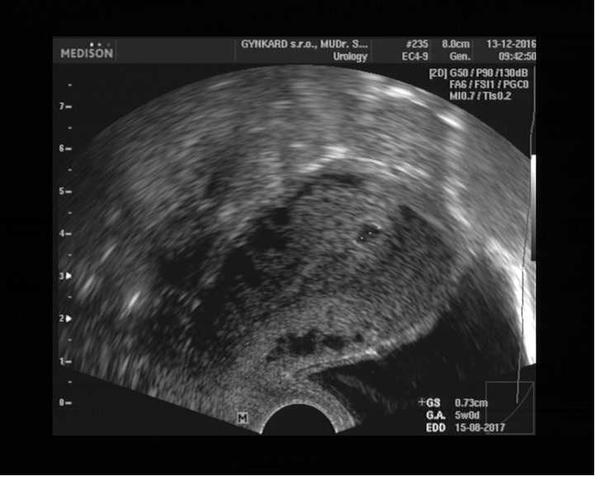

@evzenie2016 Ahojky tak podávám info... dneska jsem byla u pana gynekologa miminko tam je 😍jsem v 7.týdnů a moc děkuji za podporu a pro radost přidávám fotečku mojí malé fazolky 😍